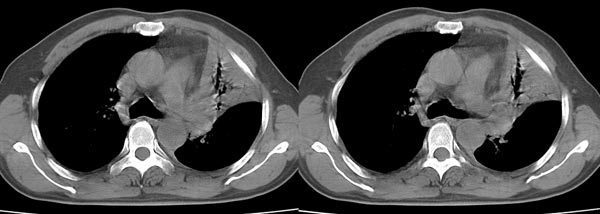

以下是引用dyqct在2006-4-1 22:20:00的发言:[br]左肺上叶明显萎陷、实变,支气管大部通畅,部分扩张,部分壁似见串珠状钙化。主动脉弓旁见肿大淋巴结。纵隔左移。左侧胸壁后缘见新月形高密度,边界清楚。[br] 考虑:1、左肺上叶肺不张伴支气管扩张(牵拉性),可能为支气管内膜结核所致。[br] 2、左侧少量胸腔积液。[br]

以下是引用piao001在2006-4-2 14:13:00的发言:[br]左肺上叶不全性不张,其内见钙化及扩张支气管,结合病史,考虑支气管内膜结核。建议支气管镜明确检查。